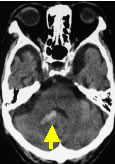

小脳出血